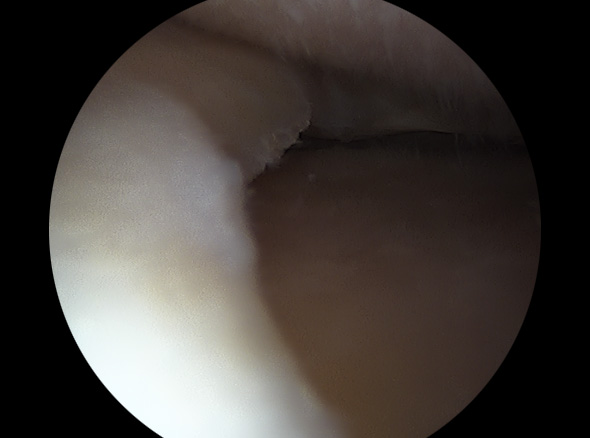

지속적인 증상이 동반된 반월상 연골판 파열에 적용하는 수술적 치료방법입니다.

불안정한 반월상연골 부위를 내시경으로 확인하여 파열된 연골판을 꿰맴

반월상 연골판 파열 정도에 따라서 절제술, 봉합술로 나눠 수술을 결정합니다.